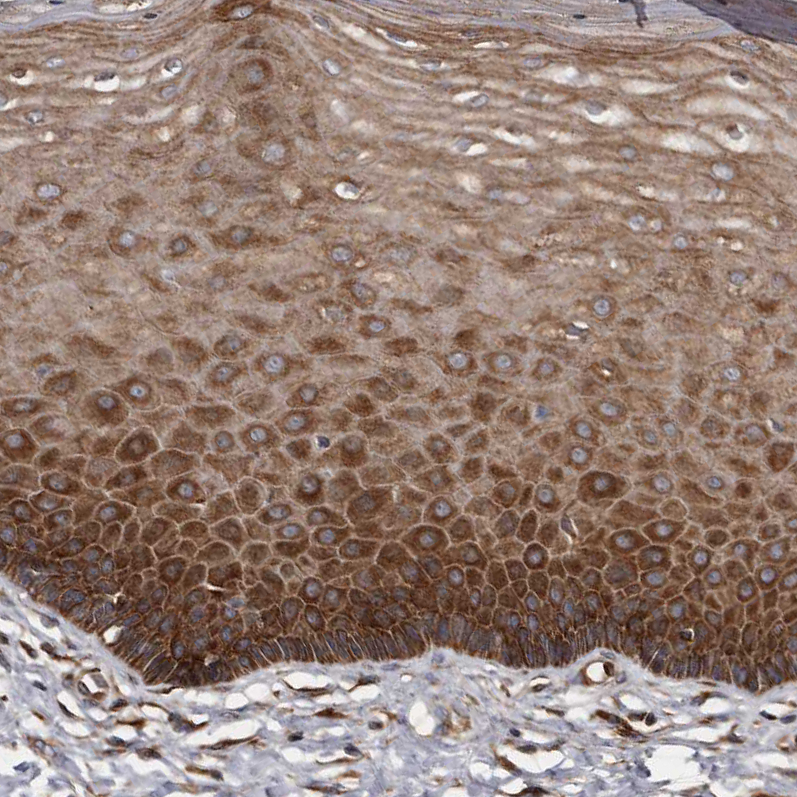

Immunohistochemical staining of human prostate shows strong cytoplasmic positivity in smooth muscle cells.